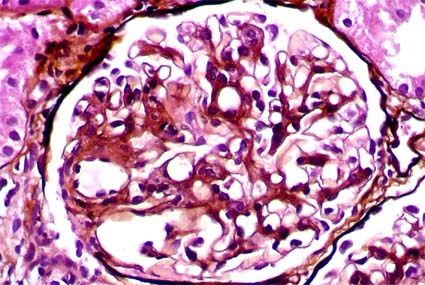

Con diagnóstico de LES se hace

biopsia renal para determinar compromiso por la enfermedad. Observe

las imágenes.

Figura 2.

H&E, X400.